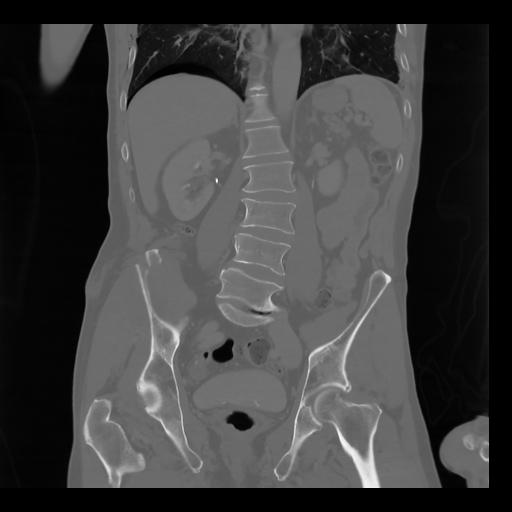

35 CUERPO,CE,Coronal,3.000,CUERPO,Coronal,